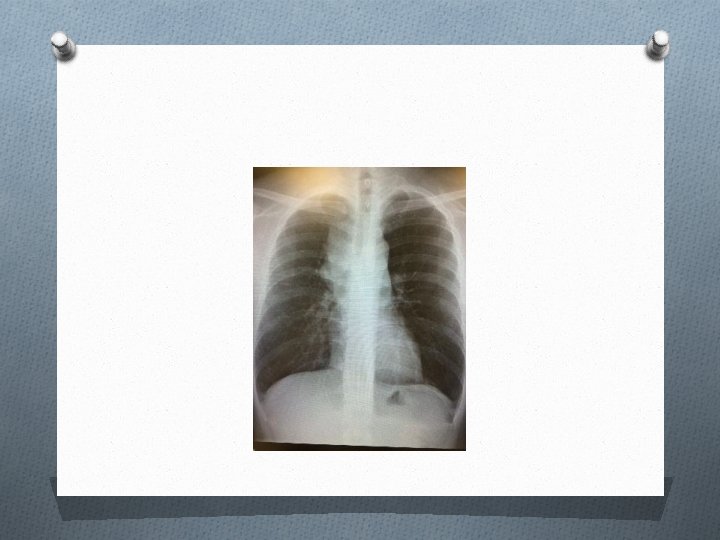

Case 4 O M/44 O Non-smoker O c/o gradual onset dyspnea, headache, sensation of face and throat swelling especially during supine position for 1 week O BP 124/76 mm. Hg, P 94/min, Sp. O 2 97% (RA)

Question 1 O What is the diagnosis? (1 mark)

Question 2 O Name 2 life-threatening conditions associated with the syndrome. (1 mark)

Question 3 O Suggest 3 causes of the syndrome. (1. 5 marks)

Question 4 O Suggest 1 further investigations for this patient to delineate the cause. (0. 5 mark)

Question 5 O Suggest 2 treatments in this case. (1 mark)